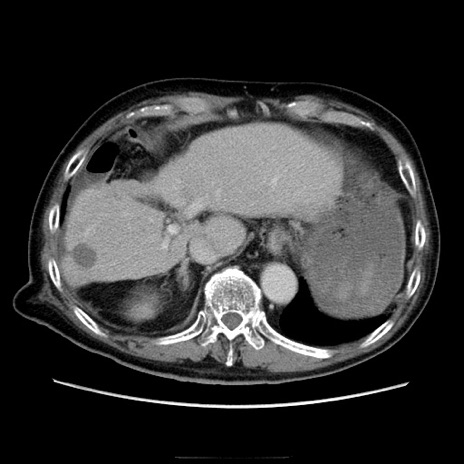

症例21(横断像)

【症例】70歳代男性

【主訴】腹痛

【現病歴】肝硬変・肝細胞癌にてかかりつけの方。約9時間前に食後より腹痛出現。症状が徐々に増悪し、嘔吐出現したため来院。

【既往歴】肝硬変、肝細胞癌(RFA、TACE後)

【身体所見】意識清明、表情苦悶様、BT 36℃、BP 129/78mmHg、P 88bpm、SpO2 97%(RA)、右上腹部から心窩部にかけて圧痛あり、反跳痛なし、筋性防御あり。

【データ】WBC 5800、CRP 0.16